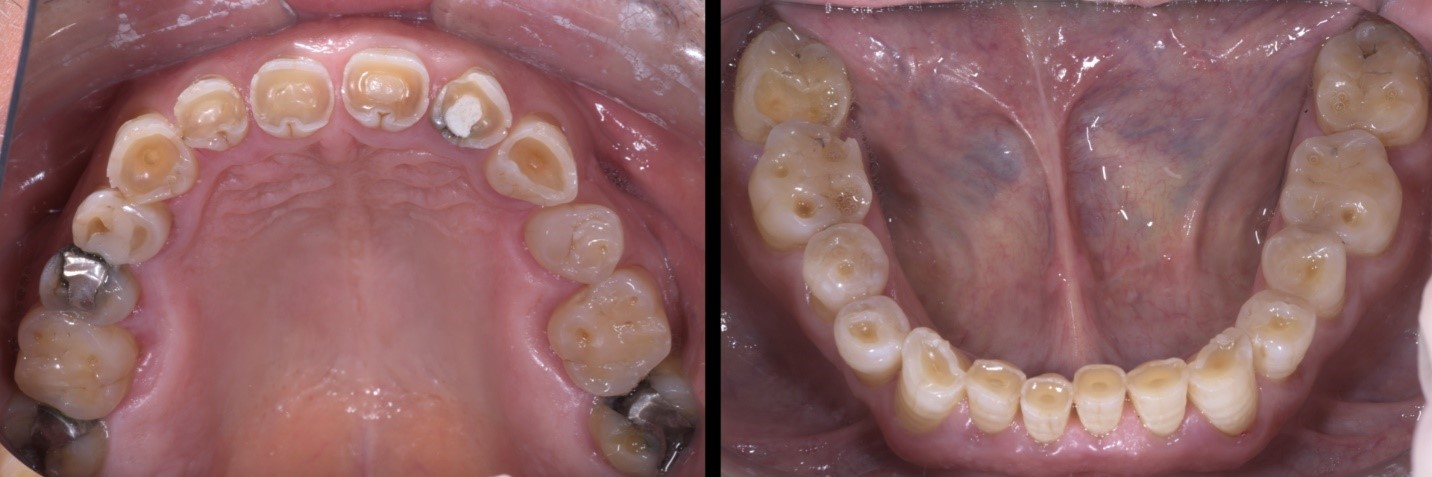

Fig. 1a e 1b

Il Paziente, di anni 69, si presenta alla mia osservazione con forti limiti estetico-funzionali dovuti a dentatura fortemente usurata.

Fig. 2a e 2b

Dopo un attento studio del caso, si opta per una riabilitazione completa con rialzo della dimensione verticale di occlusione. Il rialzo calibrato della DVO viene testato mediante mock-up per un periodo di 2 mesi.